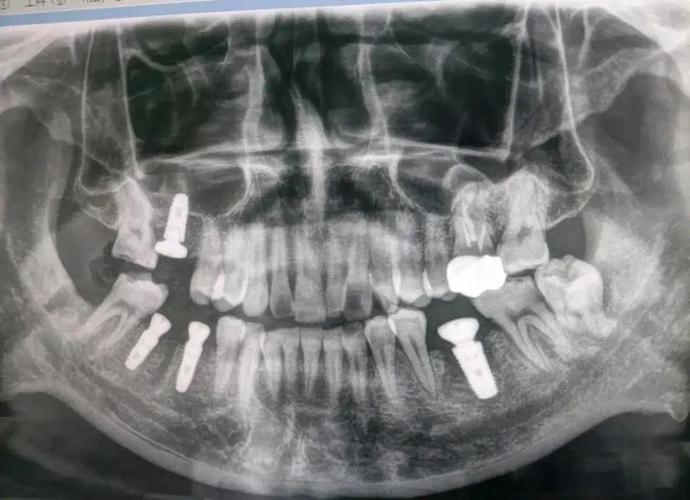

- 评估骨量:精确测量牙槽骨的高度、宽度、厚度,判断是否满足种植体植入的最低要求(通常种植体长度需8-12mm,宽度需≥5mm),若骨量不足,可提前规划骨增量手术(如植骨、上颌窦提升等)。

- 定位解剖结构:明确下颌神经管、上颌窦、颏孔等重要解剖结构的位置,避免种植术中损伤神经导致麻木,或穿透上颌窦引发感染。

- 判断骨质量:骨密度直接影响种植体的稳定性,CT可通过灰度值分析骨类型(如D1型致密骨、D2型皮质骨-松质骨混合、D3型疏松骨、D4型极度疏松骨),医生据此选择合适的种植体型号、植入扭矩及术后愈合方案。

- 设计种植方案:结合患者咬合关系、邻牙位置等信息,在CT图像上模拟种植体植入角度、深度,避开重要解剖结构,确保种植体受力合理,避免远期并发症(如种植体周围炎、修复体崩裂等)。

- 骨量评估:牙槽骨高度、宽度、厚度数据,是否达到种植标准(如下颌后牙区骨高度需≥12mm,避开下颌神经管;上颌后牙区骨高度需≥15mm,避免穿透上颌窦底)。

- 解剖结构位置:下颌神经管距离牙槽嵴顶的距离(理想≥2mm)、上颌窦底厚度(若<1mm需行上颌窦提升术)、颏孔位置(避免损伤颏神经)。

- 种植方案设计:包括种植体品牌、型号(长度、直径)、植入角度(通常与牙长轴呈15°-30°以避开邻牙牙根)、是否需植骨或使用种植导板(3D打印导板可提高植入精度0.5-1mm)。